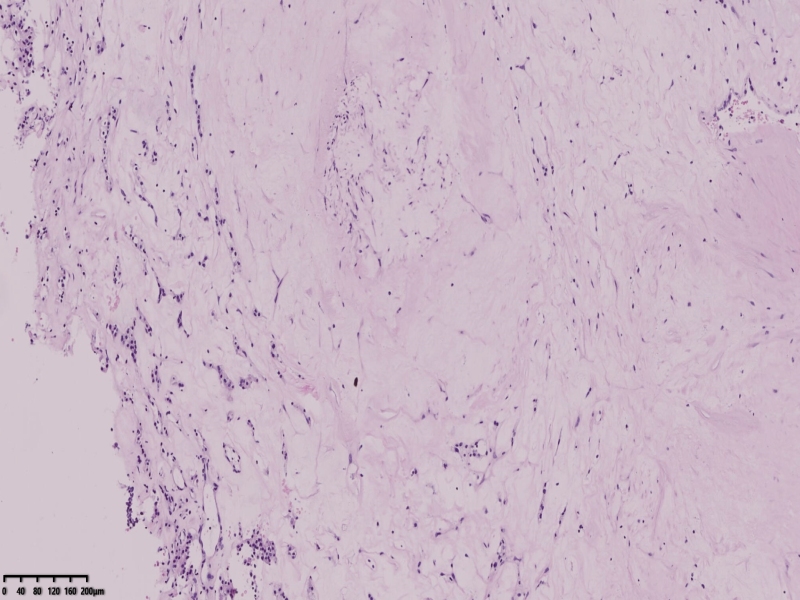

肾癌

2025-11-06 09:11 阅读(23) 评论(0) 分类:肾

这个病例取了25块。

镜下所见